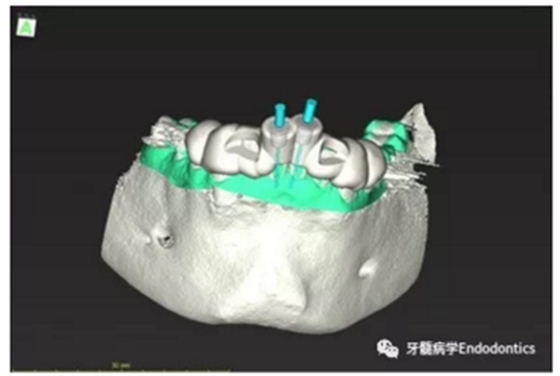

31、41叩痛明顯,牙冠變色(圖1)。溫度和牙髓電活力測(cè)試無反應(yīng)。兩張從不同角度拍攝的x線片顯示,相對(duì)于側(cè)切牙,雙側(cè)下中切牙都有嚴(yán)重的根管鈣化(圖2)。41有明顯根尖周暗影,31根尖周暗影不明顯。為進(jìn)一步證實(shí)31是否存在根尖周病變,同時(shí)精細(xì)觀察31、41的復(fù)雜結(jié)構(gòu),根據(jù)歐洲牙髓病學(xué)會(huì)CBCT應(yīng)用指南(2014),對(duì)患牙拍攝小視野、高分辨率CBCT。CBCT影像證實(shí)31、41均伴有根尖周炎和嚴(yán)重的根管鈣化(圖3)。距離根尖4mm可見根管影像。 由于患牙根管解剖結(jié)構(gòu)較為復(fù)雜,筆者決定使用特殊設(shè)計(jì)的微型鉆頭(直徑0.85mm)進(jìn)行“數(shù)字化導(dǎo)航牙髓治療”。 因此對(duì)下頜進(jìn)行口內(nèi)掃描(圖4)。用coDiagnostixTM軟件(Dental Wings Inc.,Montreal,Canada)將CBCT和口內(nèi)掃描的數(shù)據(jù)進(jìn)行處理,該軟件主要用于引導(dǎo)種植。通過該軟件對(duì)兩個(gè)掃描圖像進(jìn)行疊加后,虛擬鉆頭尖端沿牙長軸對(duì)準(zhǔn)根管下段可見部分(圖5)。三維檢查虛擬鉆的正確位置。

內(nèi)置的軟件工具可以設(shè)計(jì)鉆針導(dǎo)板(圖6)。該導(dǎo)板可以一個(gè)表面鑲嵌語言(stl-)文件導(dǎo)出,并用3D打印機(jī)(Objet Eden 260 V, Material: MED610, Stratasys Ltd.,Minneapolis, MN, USA)制作。

圖5.虛擬設(shè)計(jì)的微創(chuàng)根管入路。虛擬鉆針的尖端能到達(dá)鈣化根管X線影像中的可見部分。

圖6.設(shè)計(jì)導(dǎo)板。